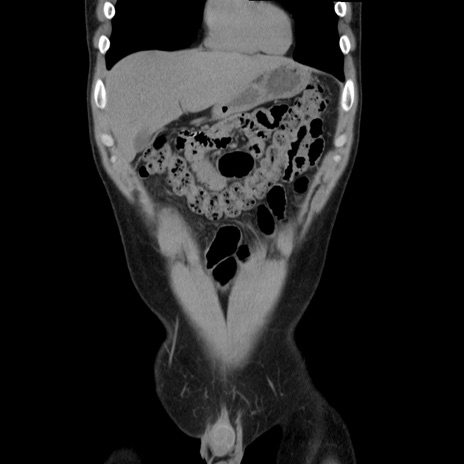

症例36(冠状断像)

【症例】20歳代 男性

【主訴】心窩部痛

【現病歴】今朝より上腹部痛あり。一旦軽快していたが再度出現したため救急要請。昨日夕に白身の魚を含む刺身を食べた。

【身体所見】BP 136/89mmHg、HR 74/min、BT 37.0℃、腹部:膨満、軟、心窩部に圧痛あり。反跳痛なし、筋性防御なし、腸雑音やや亢進あり。

【データ】WBC 17700、CRP 0.48